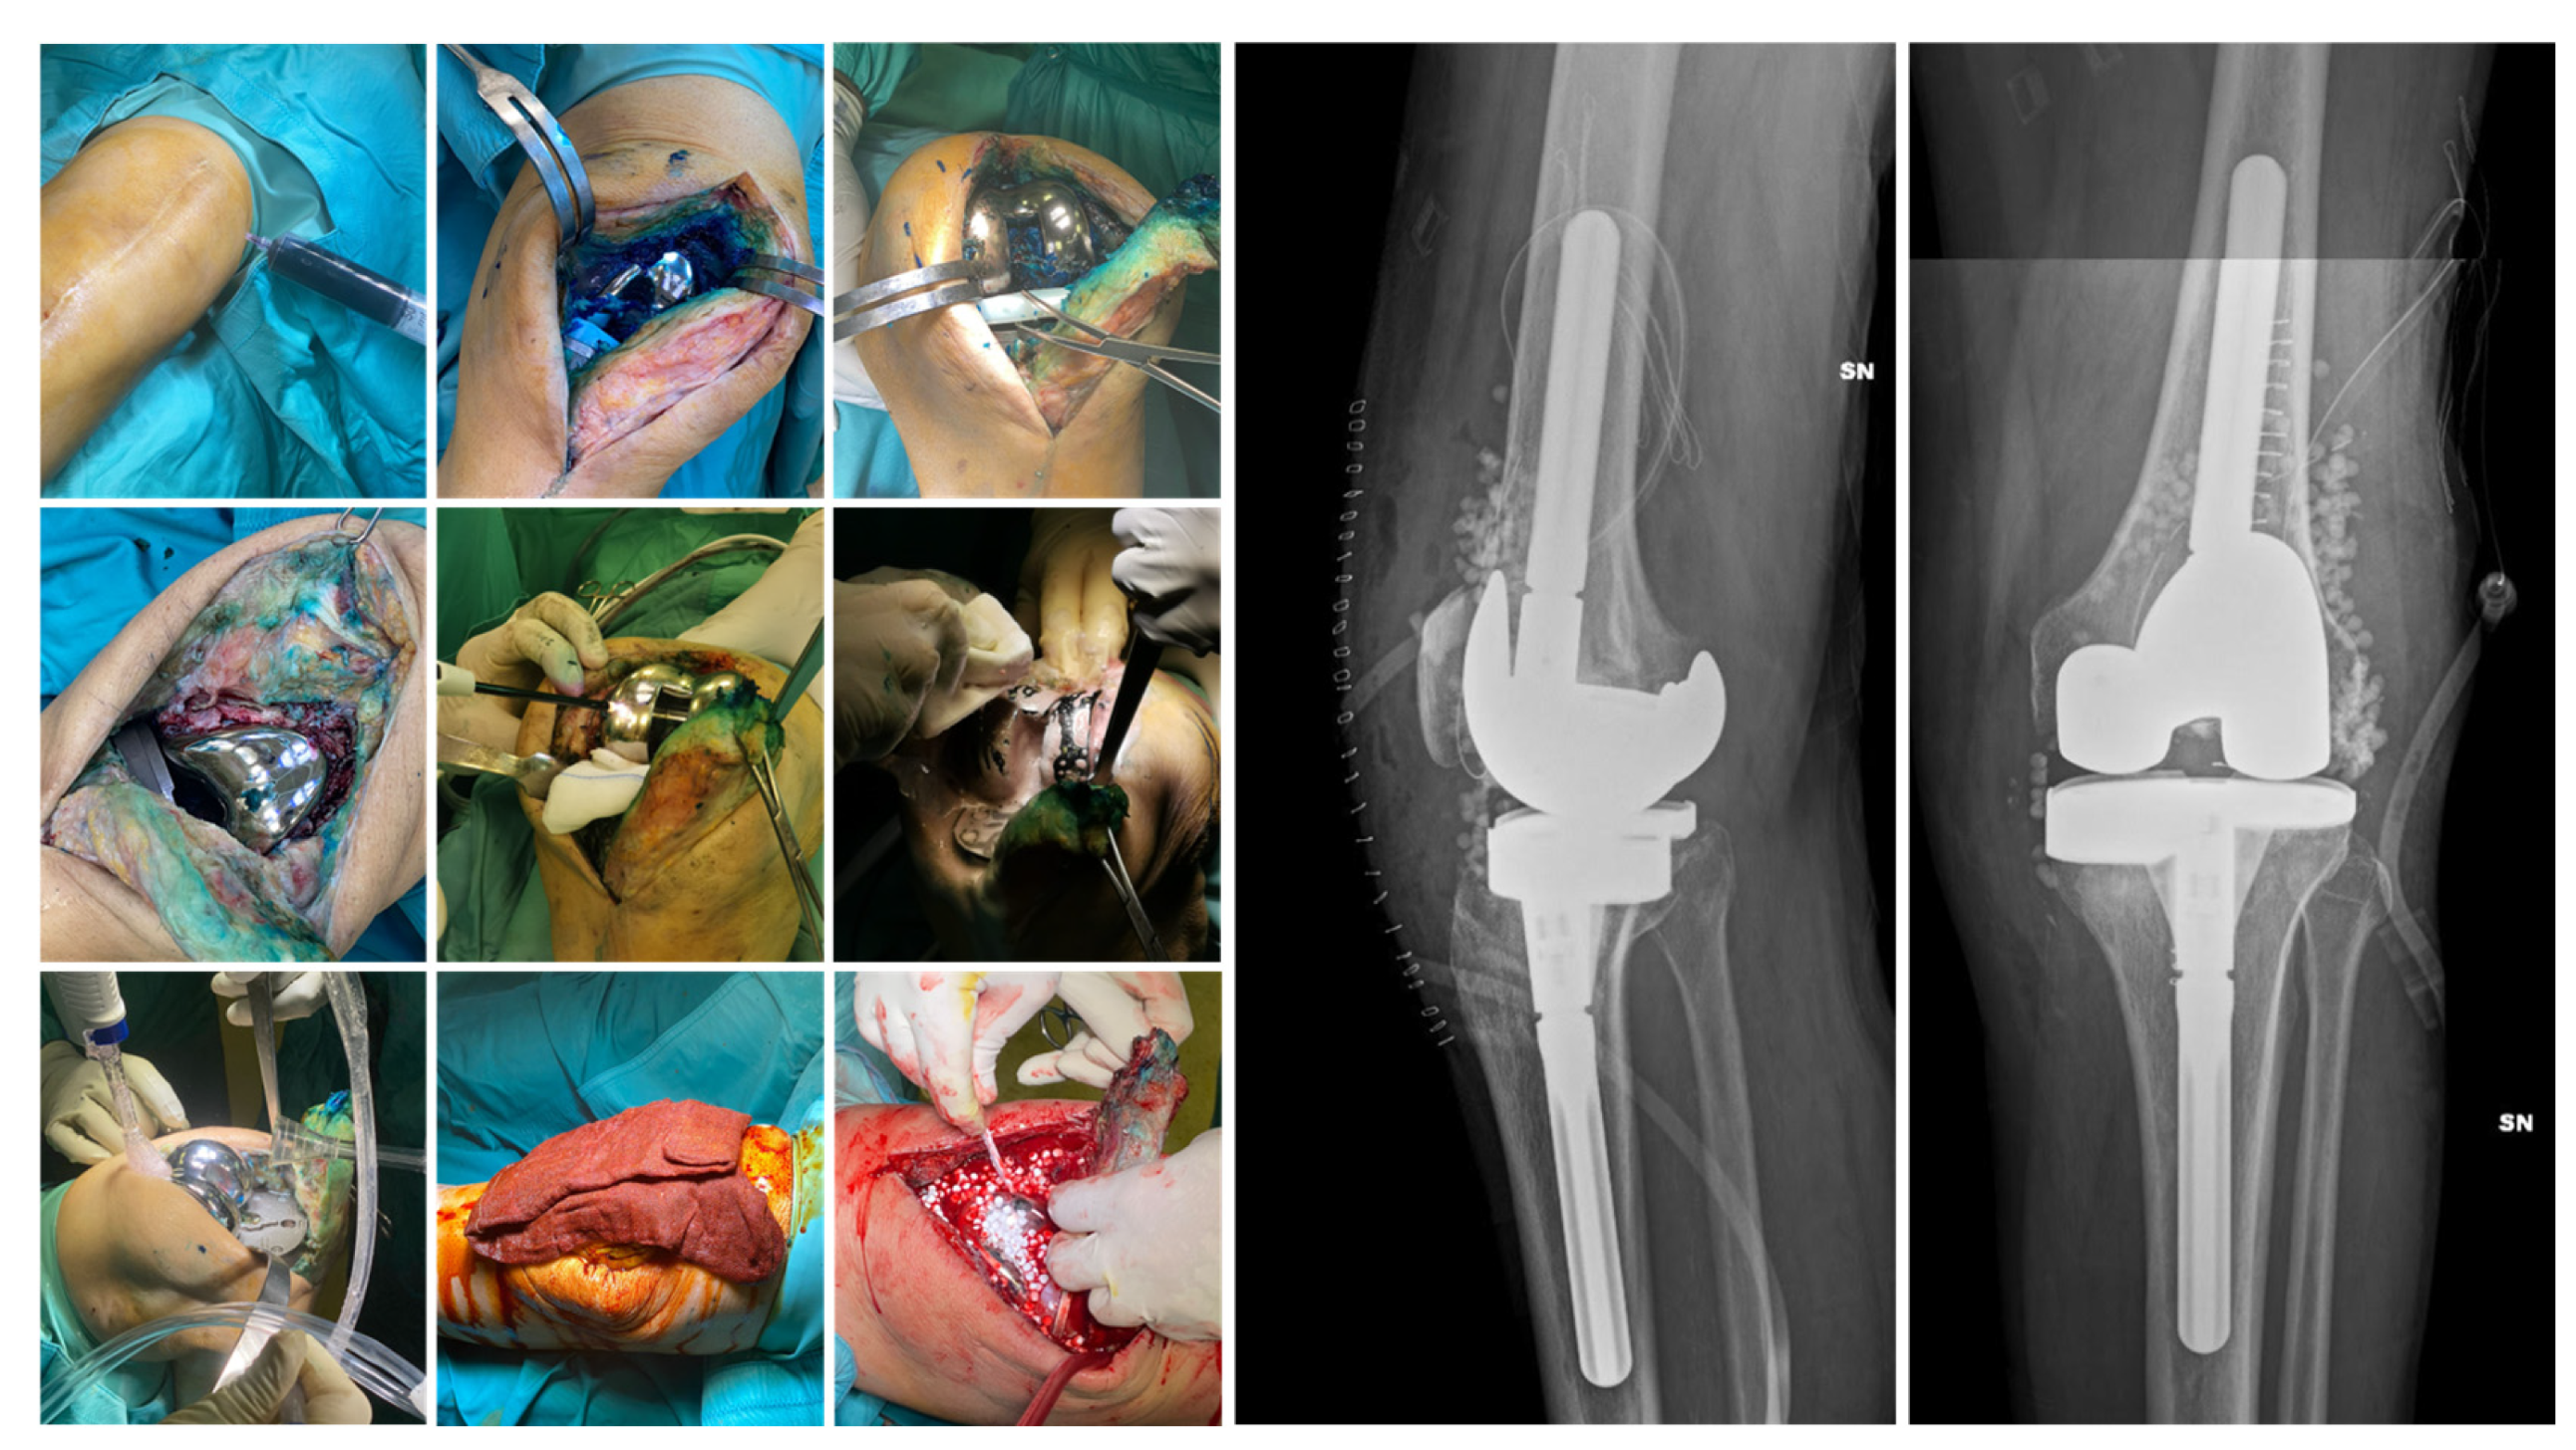

Surgical Technique. The choice of surgical procedure (DAPRI, 1-stage, 1.5-stage, or 2-stage revision) needed was based on patient-specific factors, time since the onset of symptoms and previous surgery, and the identification of an etiological agent. The DAPRI surgical procedure was performed according to the technique described by Indelli et al. [33] for the knee and adapted to the joint in question. The original technique involves the injection of a methylene blue solution into the joint to highlight contaminated areas, followed by aggressive debridement and a combined thermal (argon plasma coagulator, APC) and mechanical (brush impregnated with 4% chlorhexidine gluconate) removal of biofilm from the metallic surfaces, along with the replacement of all mobile components of the prosthesis (Figure 2).

Figure 2.

DAPRI procedure for the knee. Methylene blue solution is injected into the joint before skin incision is made and distributed with flexion–extension cycles. The polyethylene insert is removed, and a tumor-like debridement of the stained portions is performed. Thermal debridement of the prosthetic surfaces is performed with an APC, followed by mechanical debridement with a sponge soaked in 4% chlorhexidine gluconate and irrigation with normal saline and povidone–iodine solution. Finally, the insert is replaced, and calcium sulfate beads loaded with the targeted antibiotic(s) are positioned. In the postoperative X-rays the beads are visible.

In all cases, mobile components were removed, including the insert and head for hip prostheses; the polyethylene insert for knee prostheses; and the glenosphere, insert, and adapter tray for shoulder prostheses. Particular care was taken to remove all tissues stained with methylene blue, especially in hard-to-reach areas such as the posterior capsular portion of the knee. Additionally, attention was paid to the precise use of an APC on all metallic surfaces. Surgical procedures adhered to the following protocol. Patients underwent meticulous debridement, and at least 7 tissue samples were collected from different areas for microbiological analysis, alongside the explanted prosthetic components or antibiotic-loaded spacers. In all surgeries, calcium sulfate carriers (Stimulan®, Biocomposite, Keele, UK) were used, impregnated with the most appropriate antibiotic/antibiotics based on antibiogram results, or with broad-spectrum antibiotics if the pathogen was unknown. Stimulan® was selected due to its therapeutic flexibility, as it is not preloaded with a specific antibiotic. This feature allows customization of the antibiotic choice according to the patient’s profile and the type of infection, enabling the use of a wide range of antibiotics and tailoring therapy to individual clinical needs. Calcium sulfate carrier was used in all cases in the form of beads, which were placed within the joint space and, in 2-stage revision procedures, also within the medullary canals at the time of spacer implantation. Since the antibiotic used was not the same in all procedures—being either tailored to the antibiogram or selected as a broad-spectrum agent—the preparation method was modified accordingly, based on the manufacturer’s instructions. At the end of the procedure, to control bleeding and in the absence of contraindications, tranexamic acid was administered both intravenously and topically, as previously described [34].